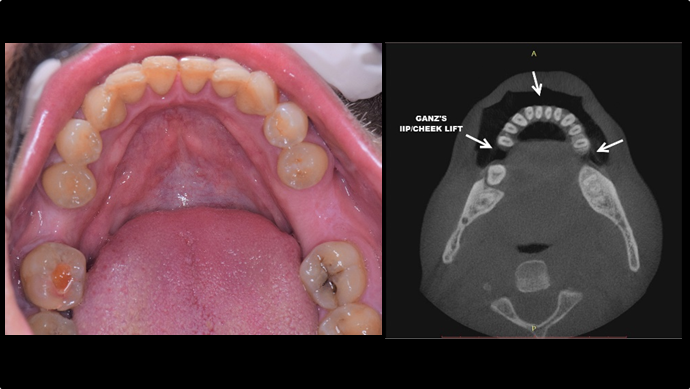

“Automated customized drilling protocols for optimum implant stability/ ONE-DAY implants ”

Clinical case: : Immediate loading of lower molars using R2Gate prefabricated 3D-printed provisional restoration

- Courtesy of Dr. Sam Omar, Egypt -